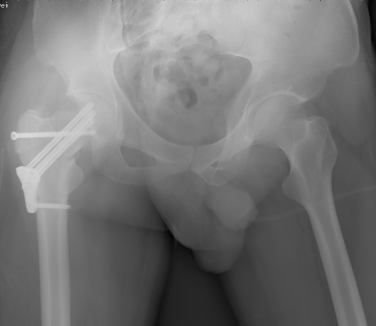

术前3D打印模型

2015年12月,一名32岁的青年男性工作时不慎从高处坠落导致股骨颈骨折(经颈型)而入住我院骨创伤与手外科,考虑该类骨折具有很高的坏死率,患者越年轻坏死率越高。“以往,该类骨折手术的实施主要依靠患者的X光片进行手术分型,但X光片的缺陷主要在于其平面化,因此往往需要医生有一个立体空间的想象力,才能为接下来的手术做好铺垫。”即使行局部骨折三维重建也难以让手术医师有个直观的感觉,无法在体外对其进行术前预演。因患者体重较肥胖,骨折移位明显,为降低患者的股骨头坏死率的发生,科室主任陈跃平教授提出使用3D打印技术的“提前干预”,通过3D打印出他的全仿真患者股骨颈进行手术预演,因为有了预演的经验,最终手术得以精准、迅速完成,耗时较以往少了一半以上,目前创伤骨科已为近10位患者成功实施手术,患者术后恢复良好。

对医生来说,3D打印技术的应用更具精准度和前瞻性。仿真模型可以发现大量隐藏的信息,方便医生进行术前评估、诊断、选择手术路径、精确手术部位及决定手术方案,可就术中应避开的人体组织、血管、神经等复杂情况进行提前演练。同时,针对外地患者的会诊,也可以通过对方医院传来的患者影像数据,用3D打印机打印出仿真实体,以此为手术提供远程指导。